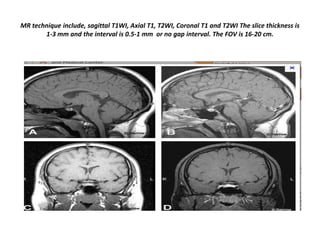

MR technique include, sagittal T1WI, Axial T1, T2WI, Coronal T1 and T2WI The slice thickness is

1-3 mm and the interval is 0.5-1 mm or no gap interval. The FOV is 16-20 cm.